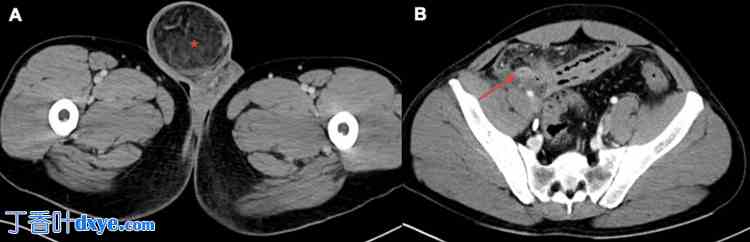

腹部和盆腔计算机断层扫描 (CT) 显示右侧腹股沟疝,疝内含脂肪,阑尾增大且发炎,并突入疝囊,同时可见腔外气体、少量腹水、腹膜炎症改变以及弥漫性肠管增厚(图 1 和图 2)。

图 2. 腹部和盆腔轴向(A 和 B)图像,静脉注射造影剂后显示右侧阿米安疝伴阑尾炎穿孔。

X 线影像显示发炎的阑尾(红色箭头)突入疝囊(红色星号)。

CT:计算机断层扫描